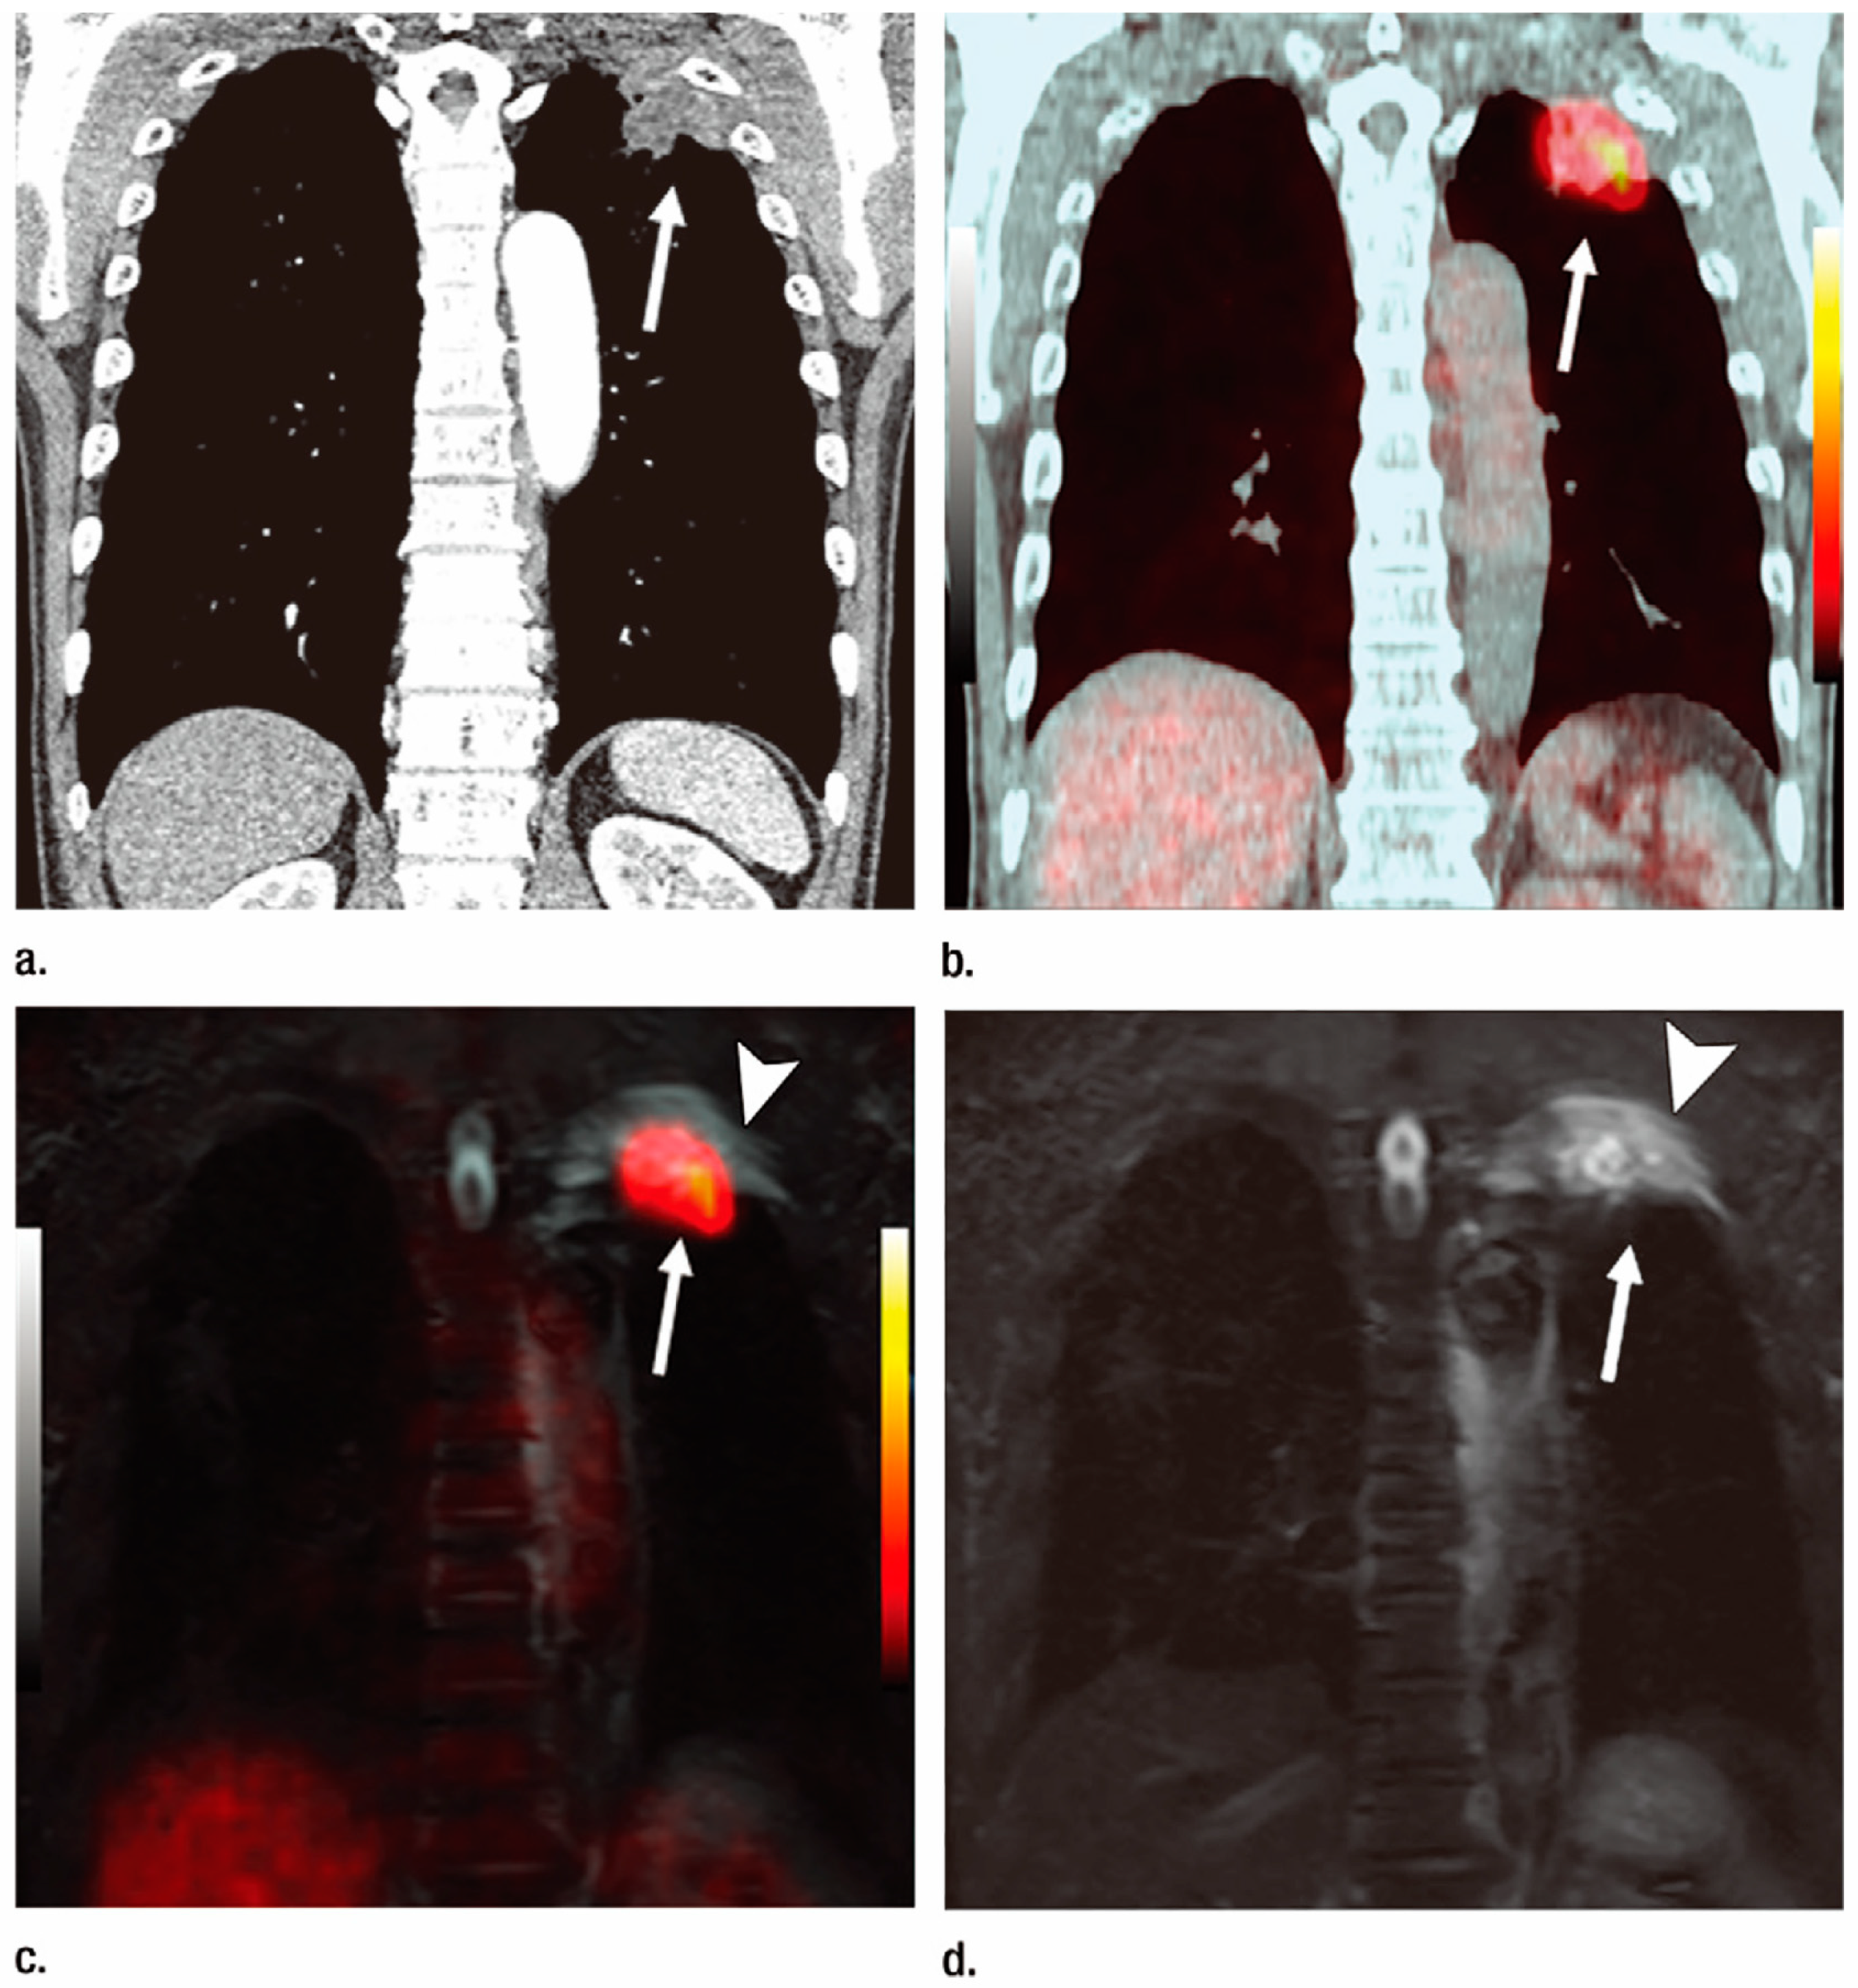

- Ohno, Y.; Koyama, H.; Onishi, Y.; Takenaka, D.; Nogami, M.; Yoshikawa, T.; Matsumoto, S.; Kotani, Y.; Sugimura, K. Non-small cell lung cancer: Whole-body MR examination for M-stage assessment–utility for whole-body diffusion-weighted imaging compared with integrated FDG PET/CT. Radiology 2008, 248, 643–654. [Google Scholar] [CrossRef] [PubMed]

- Takenaka, D.; Ohno, Y.; Matsumoto, K.; Aoyama, N.; Onishi, Y.; Koyama, H.; Nogami, M.; Yoshikawa, T.; Matsumoto, S.; Sugimura, K. Detection of bone metastases in non-small cell lung cancer patients: Comparison of whole-body diffusion-weighted imaging (DWI), whole-body MR imaging without and with DWI, whole-body FDG-PET/CT, and bone scintigraphy. J. Magn. Reson. Imaging 2009, 30, 298–308. [Google Scholar] [CrossRef] [PubMed]